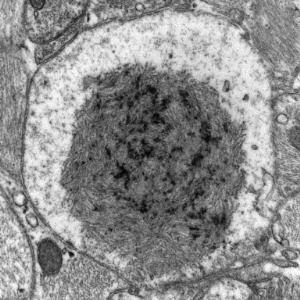

- Lafora disease

- Lafora bodies in grey matter in both neuronal perikarya and neuronal processes, mostly in the subcortical grey matter including brainstem and cerebellar nuclei

- loss of nerve cells corresponding to density of Lafora bodies

Immunohistochemistry and Ultrastructural Findings

- Lafora body reacts with antibodies against ubiquitin

- KM-279 antibody also reacts with Lafora bodies, corpora amylacea, basophilic masses in the heart, filamentous glycogen inclusions in type IV glycogenosis, and Bielschowsky bodies

- 160kD and 200kD neurofilament, and desmin antibodies also react with Lafora bodies

- still unclear if mutant Laforin is in the Lafora bodies

- Lafora bodies - in neuronal perikarya and dendrites

Lafora bodies (temporal lobectomy)